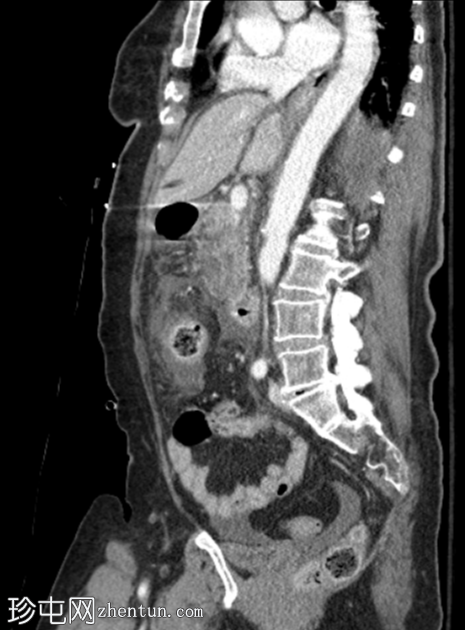

矢状位增强扫描(门静脉期)

胰腺弥漫性肿大,实质呈不均匀强化,胰头、胰体远端和胰尾可见大片无强化坏死区域(坏死胰腺实质>50%)。胰周脂肪间隙模糊,胰周、肠系膜根部、左右肾前间隙可见多发性急性坏死灶(ANC)。

门静脉、脾静脉和肠系膜静脉通畅。未见血管并发症。

轻度腹腔和盆腔腹水,伴大网膜和腹膜增厚及模糊影。

胆囊和胆总管壁增厚及强化,可能为反应性改变。

该病例表现为急性坏死性胰腺炎,伴大面积无强化实质坏死(>50%胰腺实质),以及急性胰周坏死积液(ANC持续时间<4周)。Balthazar评分E级,胰腺坏死>50%,CT严重程度指数10。胰酶升高确诊。患者紧急入住ICU。